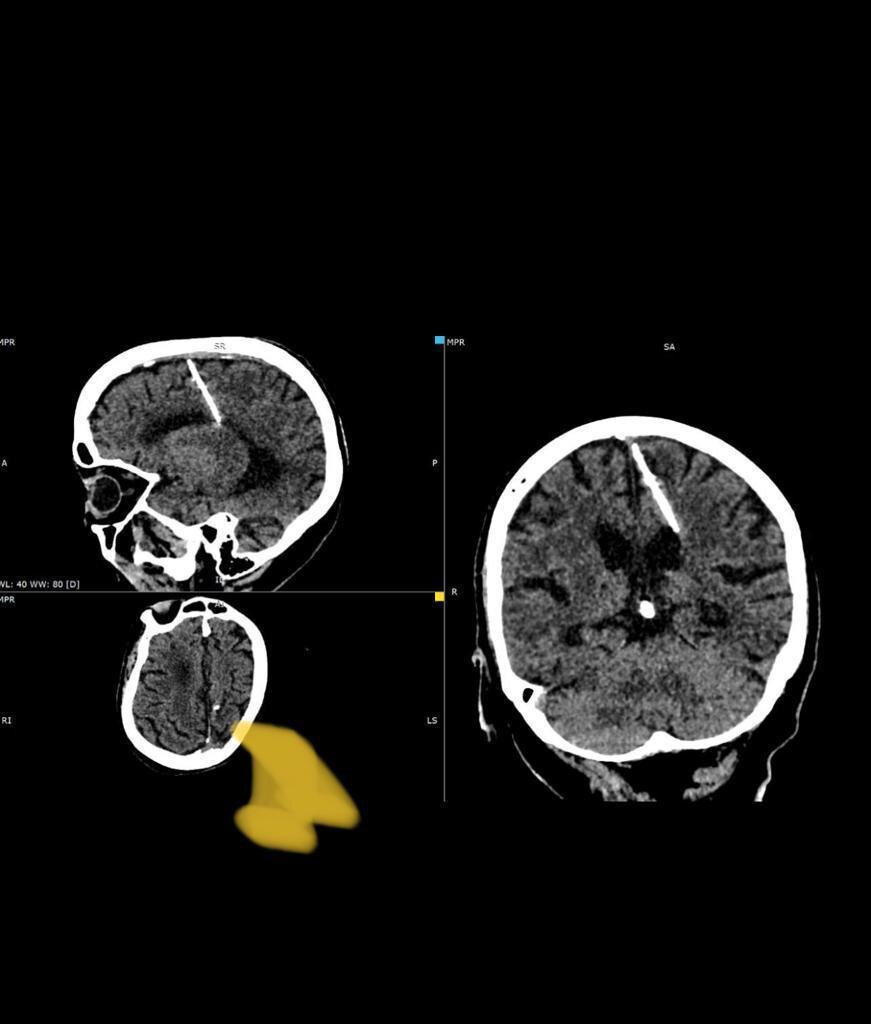

Жительница Сахалина 80 лет провела с иглой в мозгу. Это «подарок» от родителей Сахалинский минздрав рассказал невероятную историю 80-летней женщины 4 октября. Во время обследования рентгенологи случайно нашли у пенсионерки трехсантиметровую иглу в мозгу. Инородное тело ее никак не беспокоило. Игла оказалась в голове женщины сразу после рождения. В тяжелые военные годы родители решили ее умертвить. Избавление от младенца при помощи иглы, рассказывают в минздраве, в те времена не было редкостью. Ее вставляли в родничок, который впоследствии быстро затягивался, не оставляя следов прокола, а сама иголка приводила к смерти новорожденного. Жительнице Сахалина невероятно повезло, она выжила. Более того, пациентка призналась, что никогда не испытывала головных болей. На сегодняшний день игла никак не угрожает здоровью пенсионерки. Оперативное же вмешательство, напротив, может навредить. Поэтому врачи оставили инородное тело в мозгу пациентки.

Сахалинский минздрав рассказал невероятную историю 80-летней женщины 4 октября. Во время обследования рентгенологи случайно нашли у пенсионерки трехсантиметровую иглу в мозгу. Инородное тело ее никак не беспокоило.

Игла оказалась в голове женщины сразу после рождения. В тяжелые военные годы родители решили ее умертвить. Избавление от младенца при помощи иглы, рассказывают в минздраве, в те времена не было редкостью. Ее вставляли в родничок, который впоследствии быстро затягивался, не оставляя следов прокола, а сама иголка приводила к смерти новорожденного. Жительнице Сахалина невероятно повезло, она выжила. Более того, пациентка призналась, что никогда не испытывала головных болей.

На сегодняшний день игла никак не угрожает здоровью пенсионерки. Оперативное же вмешательство, напротив, может навредить. Поэтому врачи оставили инородное тело в мозгу пациентки.